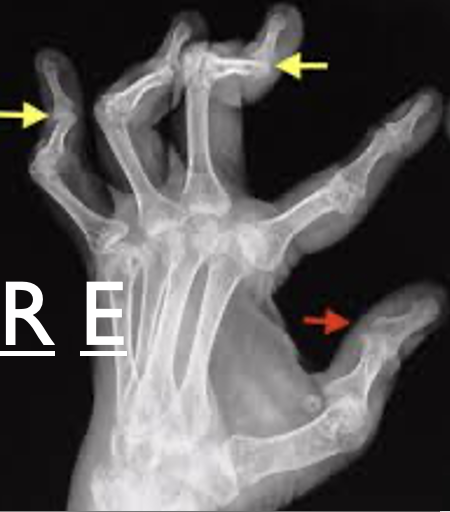

swan neck

lateral bands above axis of motion instead of staying lateral

PIP joint hyperextends as force is transmitted to the terminal tendon, hyperflexing the DIP joint

Boutonniere deformity

lateral bands below the axis of motion → forceful flexion of PIP

unable to extend PIP

happens if you drop a brick on your fingers, someone steps on your fingers